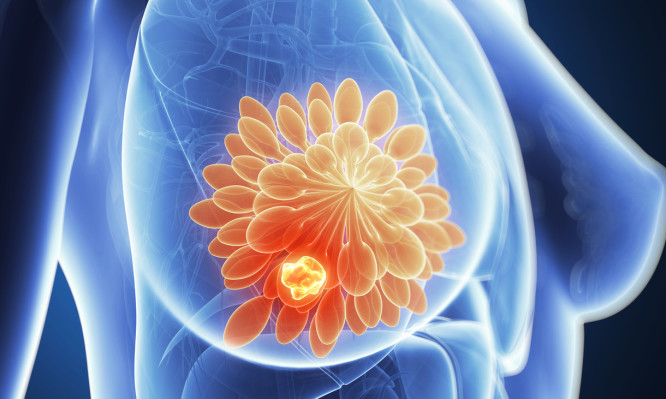

Αφαίρεση όγκου και ακτινοθεραπεία αντί για μαστεκτομή

Οι ενδείξεις για μαστεκτομή μειώνονται και η συχνότητα των συντηρητικών επεμβάσεων του μαστού αυξάνεται.

«Η ογκεκτομή σε συνδυασμό με την ακτινοθεραπεία, δείχνει να έχει ακόμα καλύτερα θεραπευτικά αποτελέσματα σε σύγκριση με τη μαστεκτομή στην προσπάθεια αντιμετώπισης του καρκίνου του μαστού.

Στοχεύουμε χειρουργικά στον όγκο, έχοντας συγχρόνως στο οπλοστάσιό μας και τα πιο σύγχρονα ακτινοθεραπευτικά μέσα που εστιάζουν με ακρίβεια χιλιοστών στο σημείο από όπου αφαιρέθηκε όγκος και στη συνέχεια σε όλο τον μαστό, με την μικρότερη δυνατή επιβάρυνση των παρακείμενων υγιών ιστών», τονίζει με έμφαση η Χειρουργός Μαστού Δρ. Φιορίτα Πουλακάκη, MD, PhD, FEBS, Διευθύντρια της Χειρουργικής Κλινικής Μαστού στην Ευρωκλινική Αθηνών.